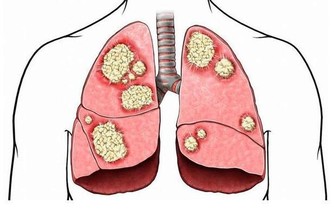

引發呼吸系統疾病:由於口腔是位於呼吸道上游的,口腔出現牙周炎,致病細菌容易“游向”呼吸道,繼而導致呼吸道感染,誘發肺部炎症,如咽喉炎、支氣管炎、扁桃體炎等。